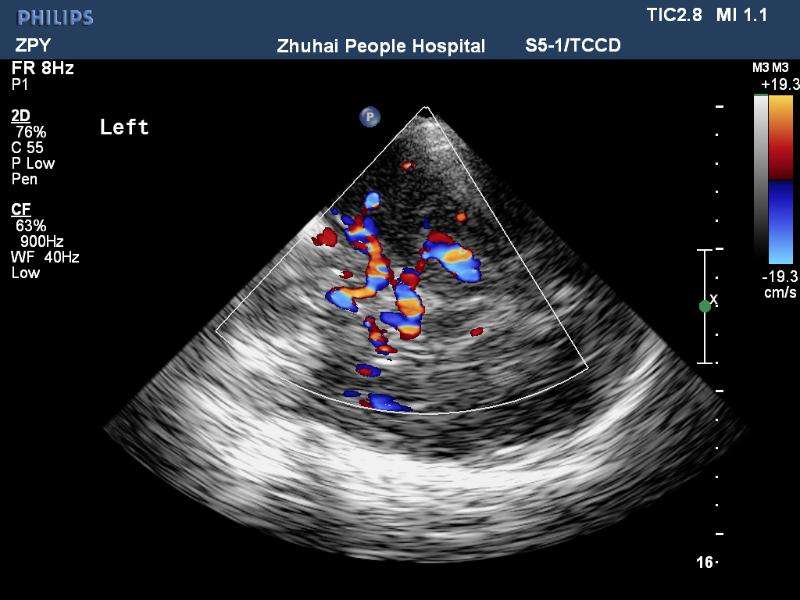

經顱彩色編碼雙功能超聲(transcranial color-coded duplex sonography

TCCD)是一種非侵入性發現顱內動脈異常血流動力學狀態的可靠方式。TCCD成像原理是在TCD基礎上增加了二維灰階實時顯像以及彩色編碼雙功能超聲成像,在二維顯示顱內解剖結構的同時,同時對運動紅細胞產生的多普勒頻移進行彩色編碼。應用TCCD檢測時可以通過在感興趣區內多點取樣,得出取樣容積內多普勒頻移曲線,通過雙側對比、左右對比以及前后對比,綜合評價缺血性腦血管病受檢者Willis環的血流動力學變化。

TCCD成像圖片

TCCD成像模式

依據多普勒頻移值編碼成像即f-TCCD:依賴運動紅細胞所產生的多普勒頻移值進行計算機編碼,可以顯示血流方向和測算血流速度,需要校正多普勒取樣角度,角度及篩查深度依賴性較大,較易產生運動偽像。(2)依據運動紅細胞所產生的總能量進行編碼成像即p-TCCD:只與運動紅細胞所產生的總能量有關,無需校正多普勒取樣角度,對于受取樣角度影響較大血管病變,諸如大腦后動脈(PCA),大腦中動脈(MCA)M2段,大腦前動脈(ACA)A1段有一定的幫助作用,信噪比更高,不易產生混疊效應。p-TCCD相對f-TCCD而言,缺點是不能顯示血流方向,對顯示狹窄處高速血流敏感性較低。